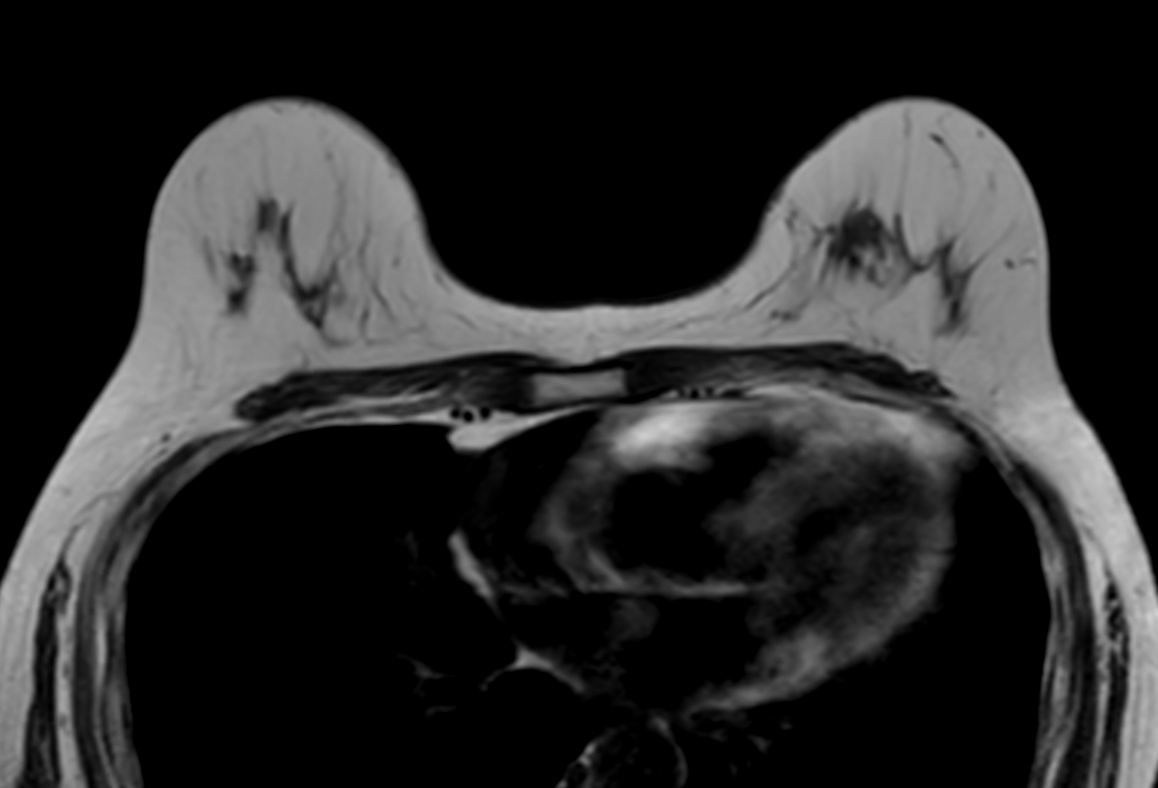

Axial T1w TSE

-